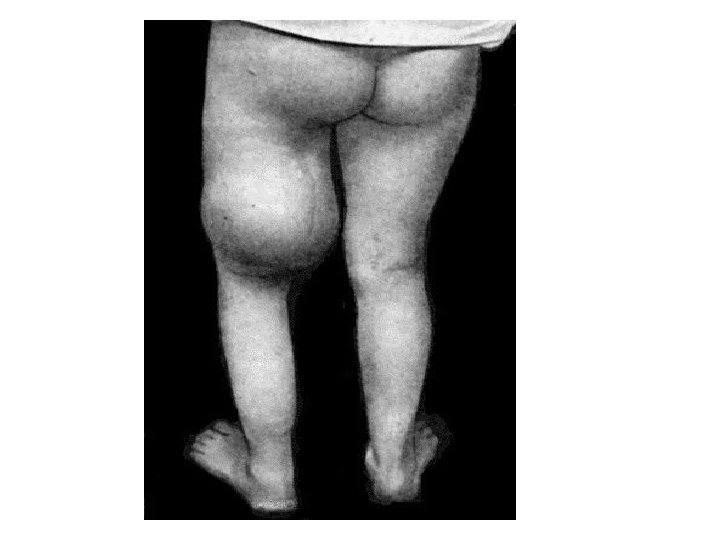

Rickets • Rickets is the softening and weakening of bones in children, usually because of an extreme and prolonged vitamin D deficiency. • Some skeletal deformities caused by rickets may need corrective surgery.